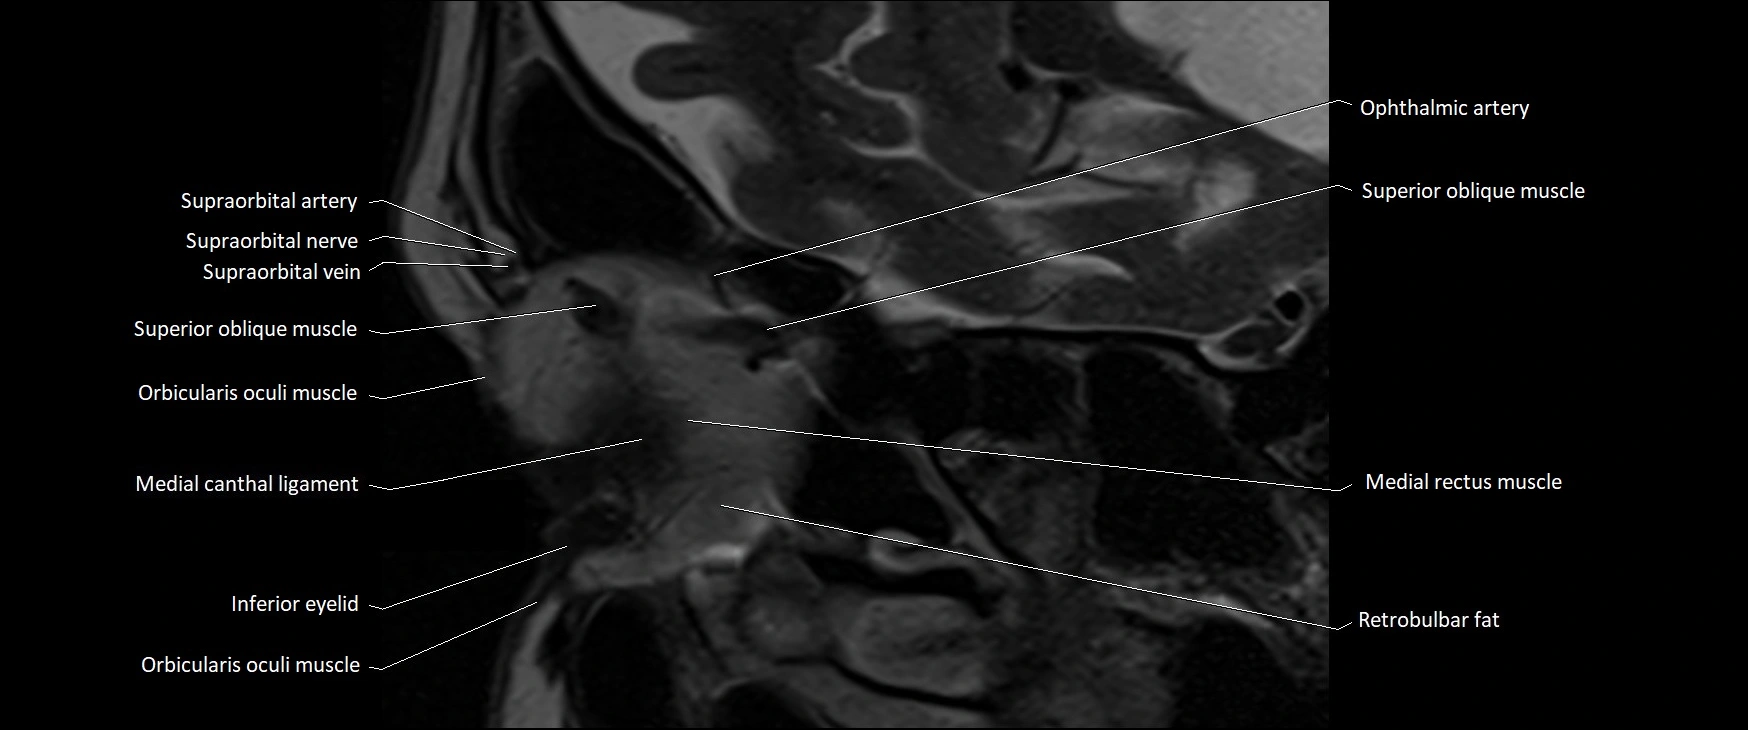

MRI images